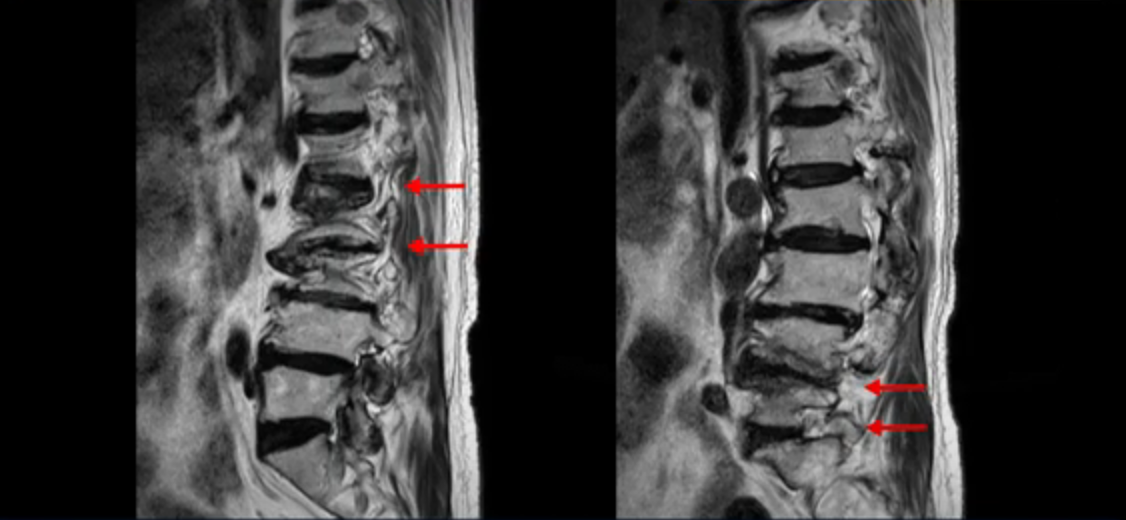

이 환자분은 허리 여러 마디가 다 안 좋아서 오랫동안 허리가 아프셨고 허리도 일찌감치 굽으셨습니다. MRI를 보시면 허리 여러 마디가 심하게 안 좋습니다.

또 신경 가지가 빠져나가는 추간공도 좁아져 있습니다. 이런 이유로 환자분의 다리가 저리고 아픈 겁니다.

또한 척추뼈 여러 개가 압박 골절과 변형으로 찌그러져 있고

골다공증도 심하시고 보시다시피 근육량이 너무 적습니다. 근육이 정상적인 분들과 비교해보면 근육이 얼마나 적은지 알 수 있습니다.

이렇게 근육도 적고 뼈가 약하신 분들 게다가 여러 마디가 안 좋은 분들은 수술하면 결과가 안 좋을 가능성이 매우 높습니다. 그래서 지방의 척추 병원과 서울의 한 최상급 대학병원에서도 수술을 안 받는 게 좋다, 수술한다 해도 위나 아래가 무너질 수 있다고 들으셨습니다.